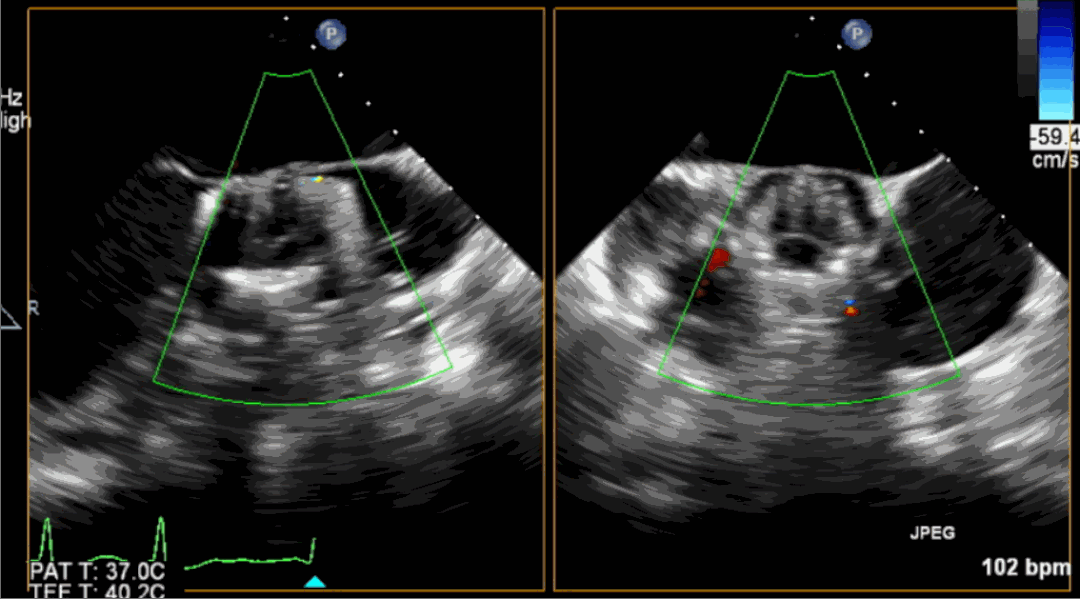

術(shù)前超聲影像圖